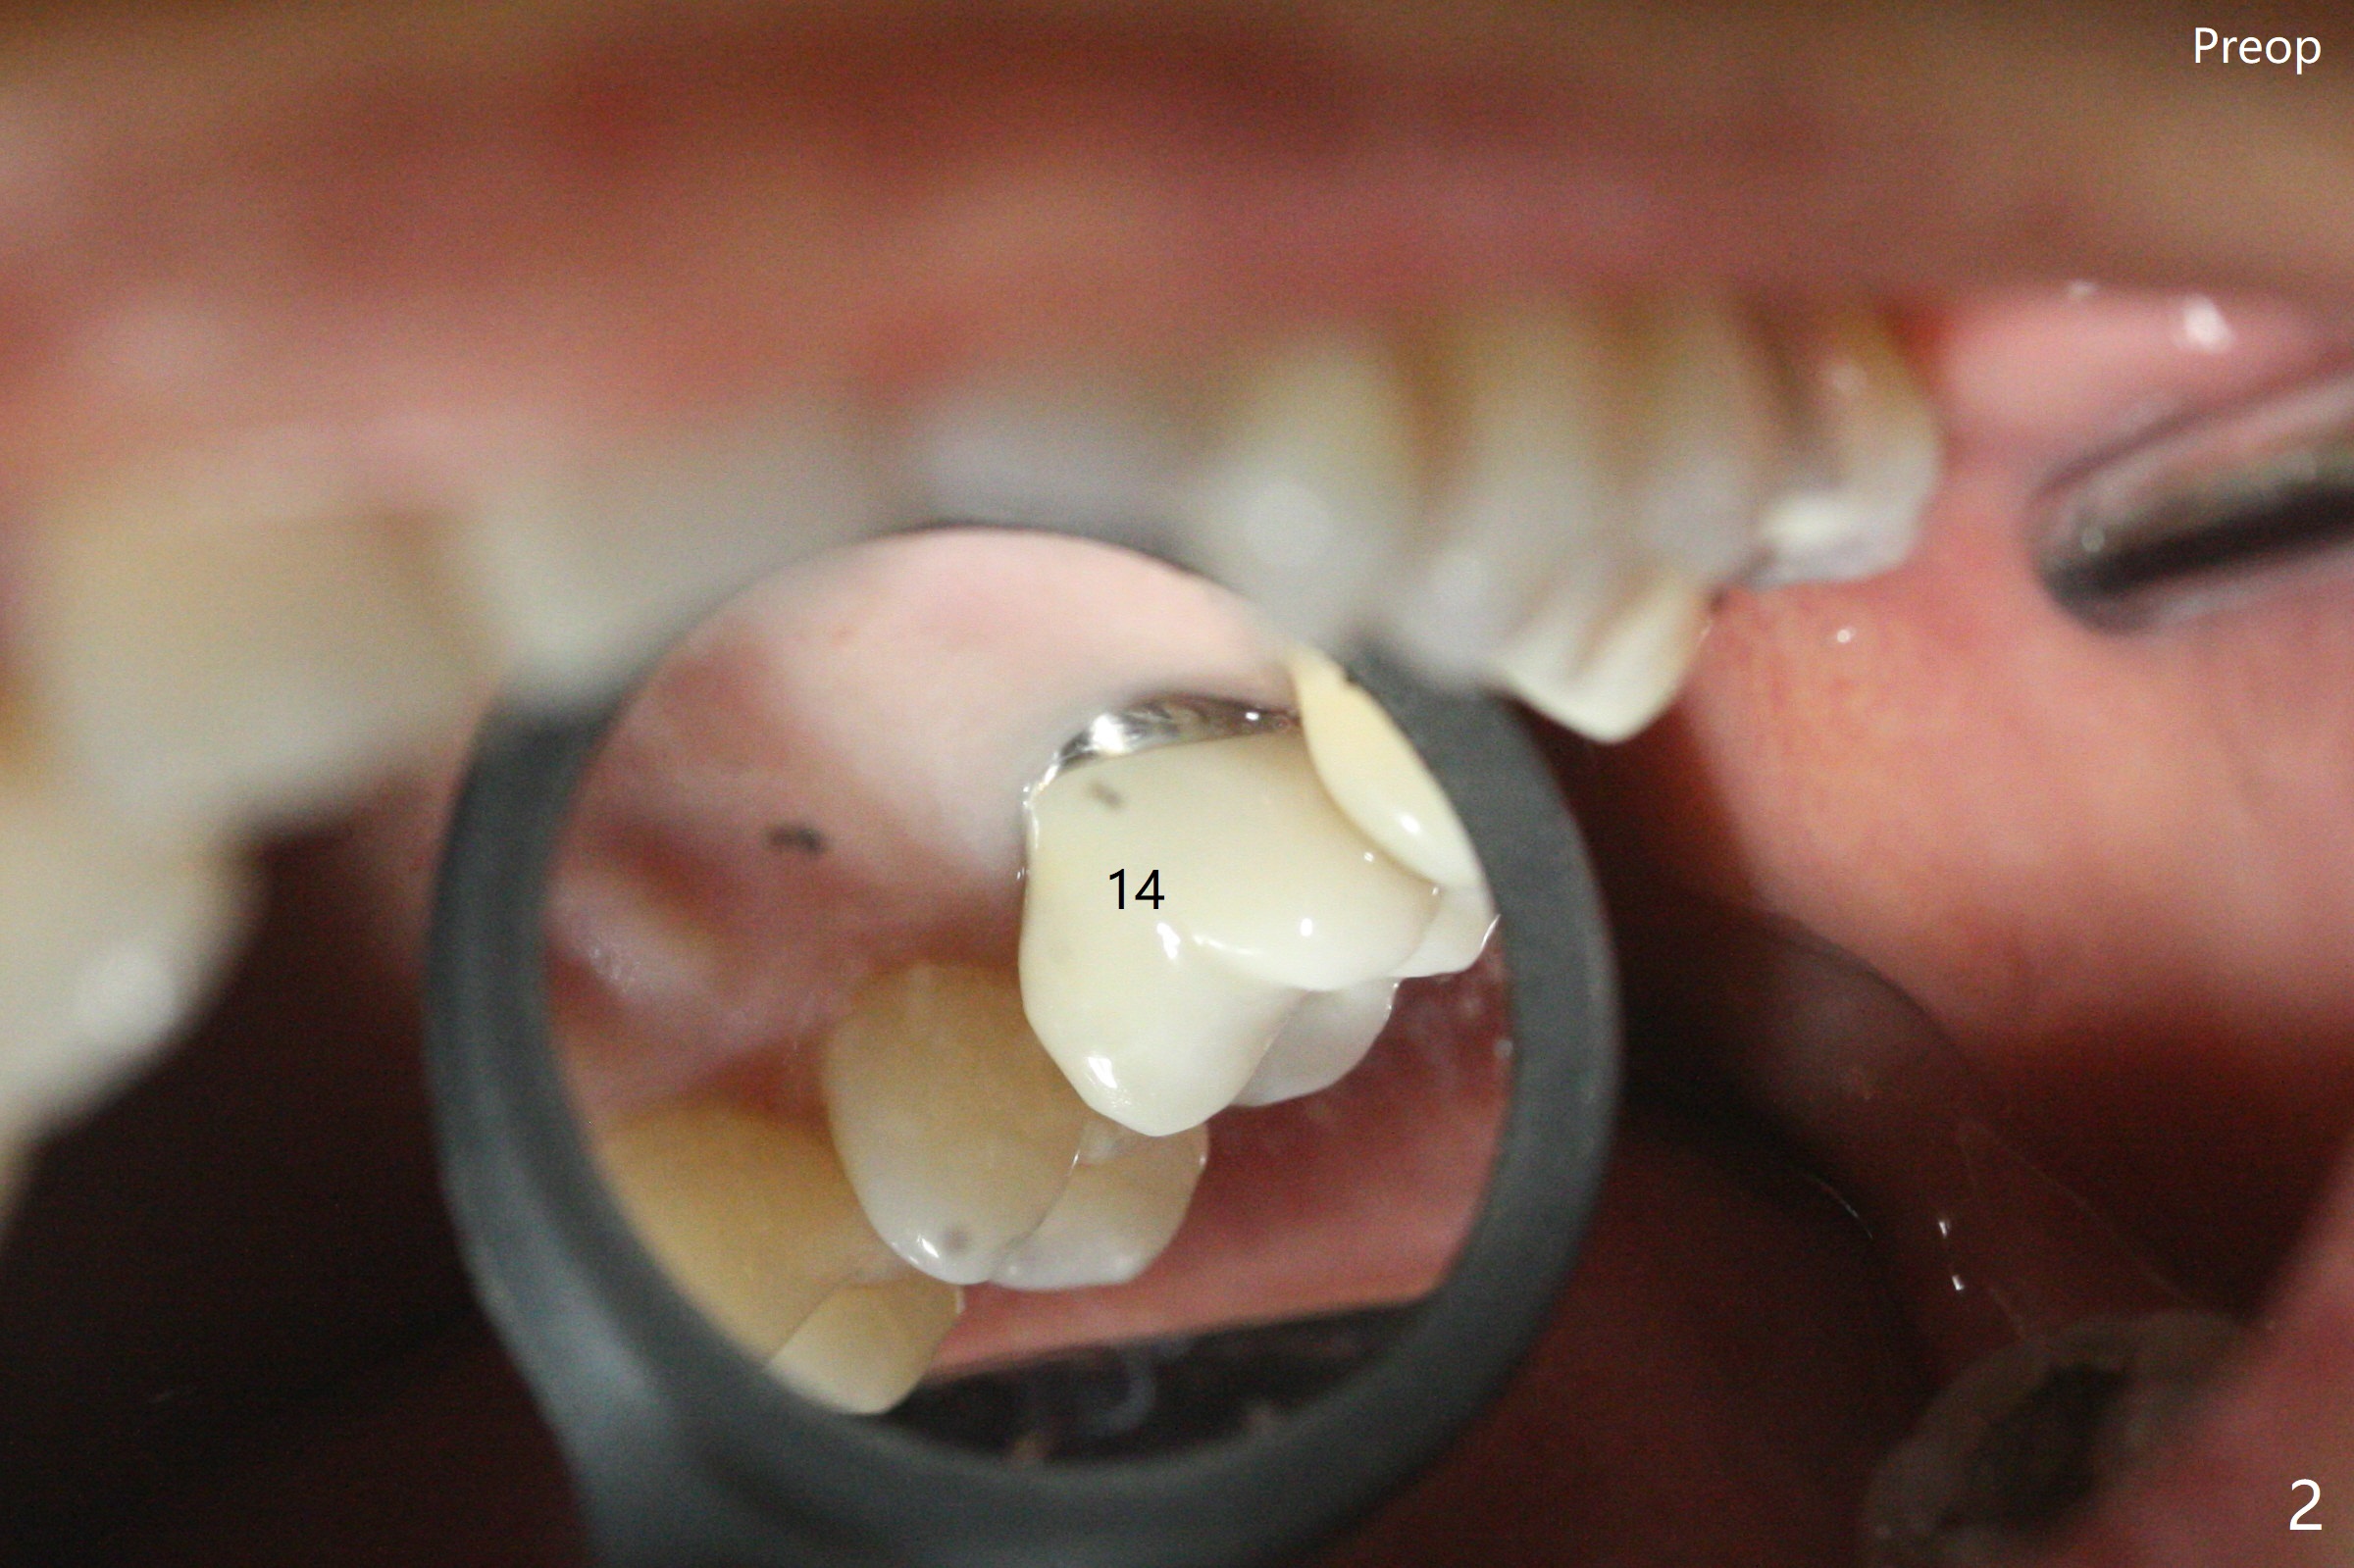

术前15号牙远中隐裂(图一:^),14号牙植体光滑面腭侧暴露(8年前腭侧窝植入),但是牙龈健康(图二)。14号牙牙槽窝没有肉芽组织,利用导板(Shinning Oral Scanner)完成3.5毫米钻洞,无法使用圆钻做内提升,改用4x10毫米报废植体提升,不幸窦膜好像破裂(因为薄),塞入半块PRF膜,促进修复,然后使用4.5x10毫米报废植体扩大植牙床(图三,四),无意达到部分提升(*),取出报废植体,发现植牙床没有穿孔了,加入少量粘性骨粉(图五:S(即使在窦内不容易分散))后,植入正式植体和基台。植体周围间隙(图五:*),使用刮匙,牙周探针,和长探针(图六)将骨粉输入深部(图七:*)。